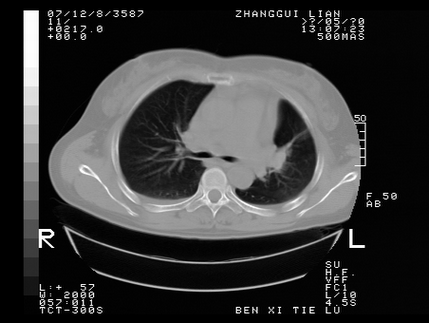

标题: CT10818:男,73,TB病史,现病史肺炎及直肠CANCER术后 [打印本页]

标题: CT10818:男,73,TB病史,现病史肺炎及直肠CANCER术后

这个请版主删除掉,这个病例我发过的,发重了,此人病史是,f,46y,胸疼,无其他原因就诊

左侧中央型肺癌伴阻塞性肺炎\\不张,左侧前上纵隔亦增宽,建议上传纵隔窗除外淋巴结转移.

考虑:左侧中央型肺癌伴阻塞性肺炎,纵隔淋巴结转移。

1)考虑为:左侧中央型肺癌伴阻塞性肺炎,纵隔淋巴结转移。2)双侧少量胸腔积液。3)心包积液。

左侧中央型肺癌伴阻塞性肺炎,纵隔淋巴结转移。

考虑左侧中央型肺癌伴阻塞性肺炎,纵隔淋巴结转移。